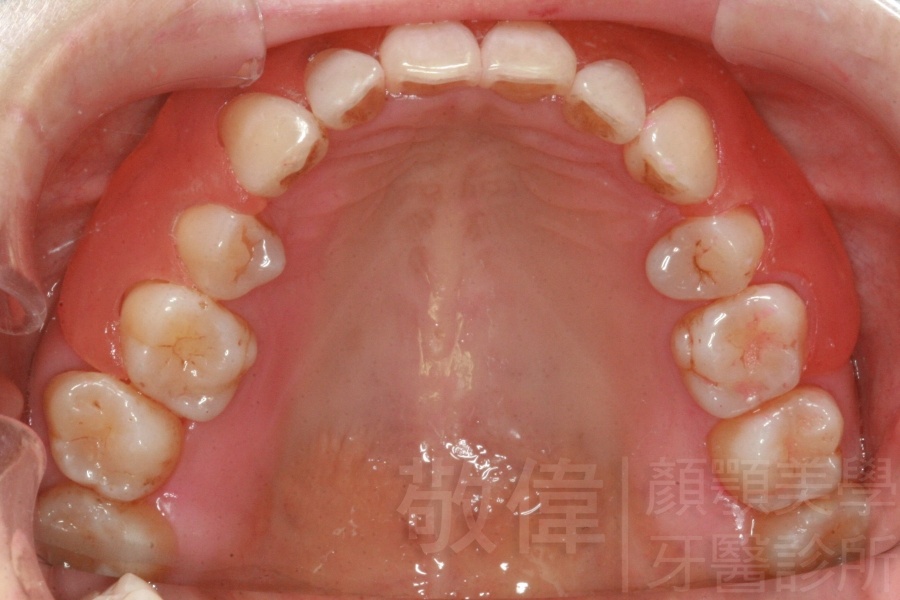

齒顏矯正/扭曲的牙弓和暴出的虎牙的矯正

矯正前-上   矯正前-下

矯正後-上   矯正後-下

<個案說明>

原來混亂歪七扭八的牙齒,尤其是暴牙(俗稱虎牙),笑起來不好看且沒有自信的笑。經由矯正之後,牙齒變的更健康,更能展現出自信的笑容。